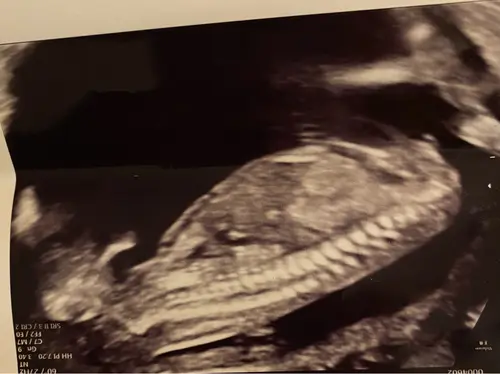

Hier geen nub te zien denk ik, toch? 13+5 🫣

En foto van het beentje, maar kan hier zelf ook niets uit halen 😆

Als het de nub is die ik denk te zien dan een meisje.